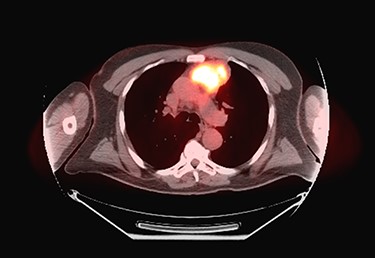

Patient’s post-operative course was notable for prolonged respiratory support due to phrenic nerve deficit. Patient’s respiratory failure resolved with 5-day course of intravenous antibiotics, spot diuresis and respiratory therapy. Patient was discharged home on post-operative day 10 day. Patient completed adjuvant radiation therapy at a total dose of 50 Gy in 25 fractions to the post-operative bed and anterior mediastinum. At 10-month follow-up, patient had no respiratory complaints with surveillance PET study showing no objective sign of tumor recurrence (Fig. 4).

Ten-month post-operative surveillance PET scan demonstrating no evidence of tumor recurrence.